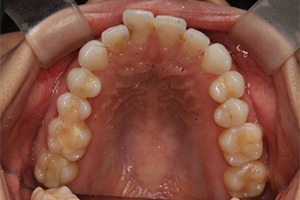

矯正治療のCASE 05

Before

After

-

- 主訴

- 歯並びがガタガタしていて清掃しにくい

- 治療内容

- ラビアル矯正(表側)

抜歯あり

- 治療費用

- 88万円~(税込)

- 治療期間

- 20か月

【リスク・副作用】

歯の痛み、口内炎、歯磨きがしにくいことによるむし歯や歯周病のリスク、歯根吸収や歯の変色、後戻りなどの副作用があります。